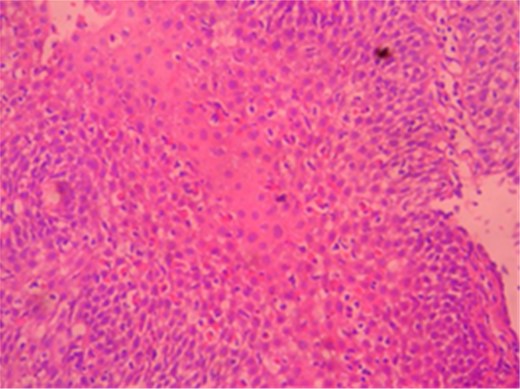

A male patient of 35 years age presented to our General Surgery Clinic with complaints of difficulty in swallowing, sensation of food sticking in the back of the breast while eating, stomach ache, weight loss and weakness for nearly a year. The fact that the symptoms chiefly arose upon ingestion of dairy products was interesting. Normal values were obtained for complete blood count serum CRP, sedimentation and total serum IgE of the patient. Standing abdominal X-ray and abdominal ultrasonography failed to reveal any evidence of pathology. Mucosal fissure and erosional areas were observed in the middle distal esophagus using upper GI endoscopy and are probably associated with reflux esophagitis; biopsies were made of the same (Fig. 1). Bulbitis and pangastritis were observed in the duodenum and stomach and biopsies were made. Pathological examinations of the endoscopic biopsies revealed evidence of chronic esophagitis in esophagus, chronic Helicobacter pylori-positive pangastritis in stomach and chronic duodenitis in the duodenum. The examination showed eosinophilic infiltration only in the esophagus (Fig. 2). Histological examination (40 X) revealed more than 30 eosinophils per field (Fig. 3). The patient was diagnosed with eosinophilic esophagitis and administered dexamethasone I.M as well as treatment for H. pylori eradication which resulted in relief of the symptoms. The patient was also instructed to avoid consumption of milk and dairy products, which caused the development of symptoms. The control endoscopic examination and pathological evaluation made after 3 months, failed to reveal evidence of esophageal eosinophilic infiltration, relapse did not occur during the following 2 years.

An accurate diagnosis of EE could be made upon observations of eosinophilic infiltration in the squamous epithelium of the esophagus. An eosinophil count of >15 per high power field (HPF) upon histological examination is generally considered sufficient for a diagnosis of EE in symptomatic patients, although the exact eosinophil count per HPF for a definite diagnosis of EO has not yet been clearly established. Moreover, eosinophilic infiltration in the mucosa of the esophagus in EE patients does not show homogeneous distribution, and employing more than one tissue sample from the middle and proximal region of the esophagus is recommended for diagnosis. Accordingly the rate of diagnosis of EE is 55% with a single mucosal biopsy, but 100% when five biopsies are utilized [6].